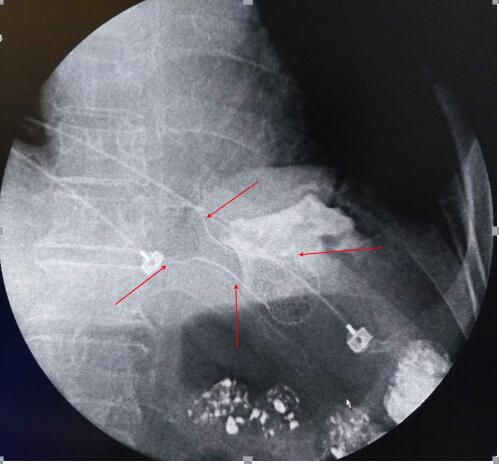

经皮选择性腹腔干造影

(黄色箭头所指为肿瘤主要供血动脉)

利用同轴微导管超选择肿瘤主要供血动脉

(图中箭头所指为肿瘤主要供血动脉)